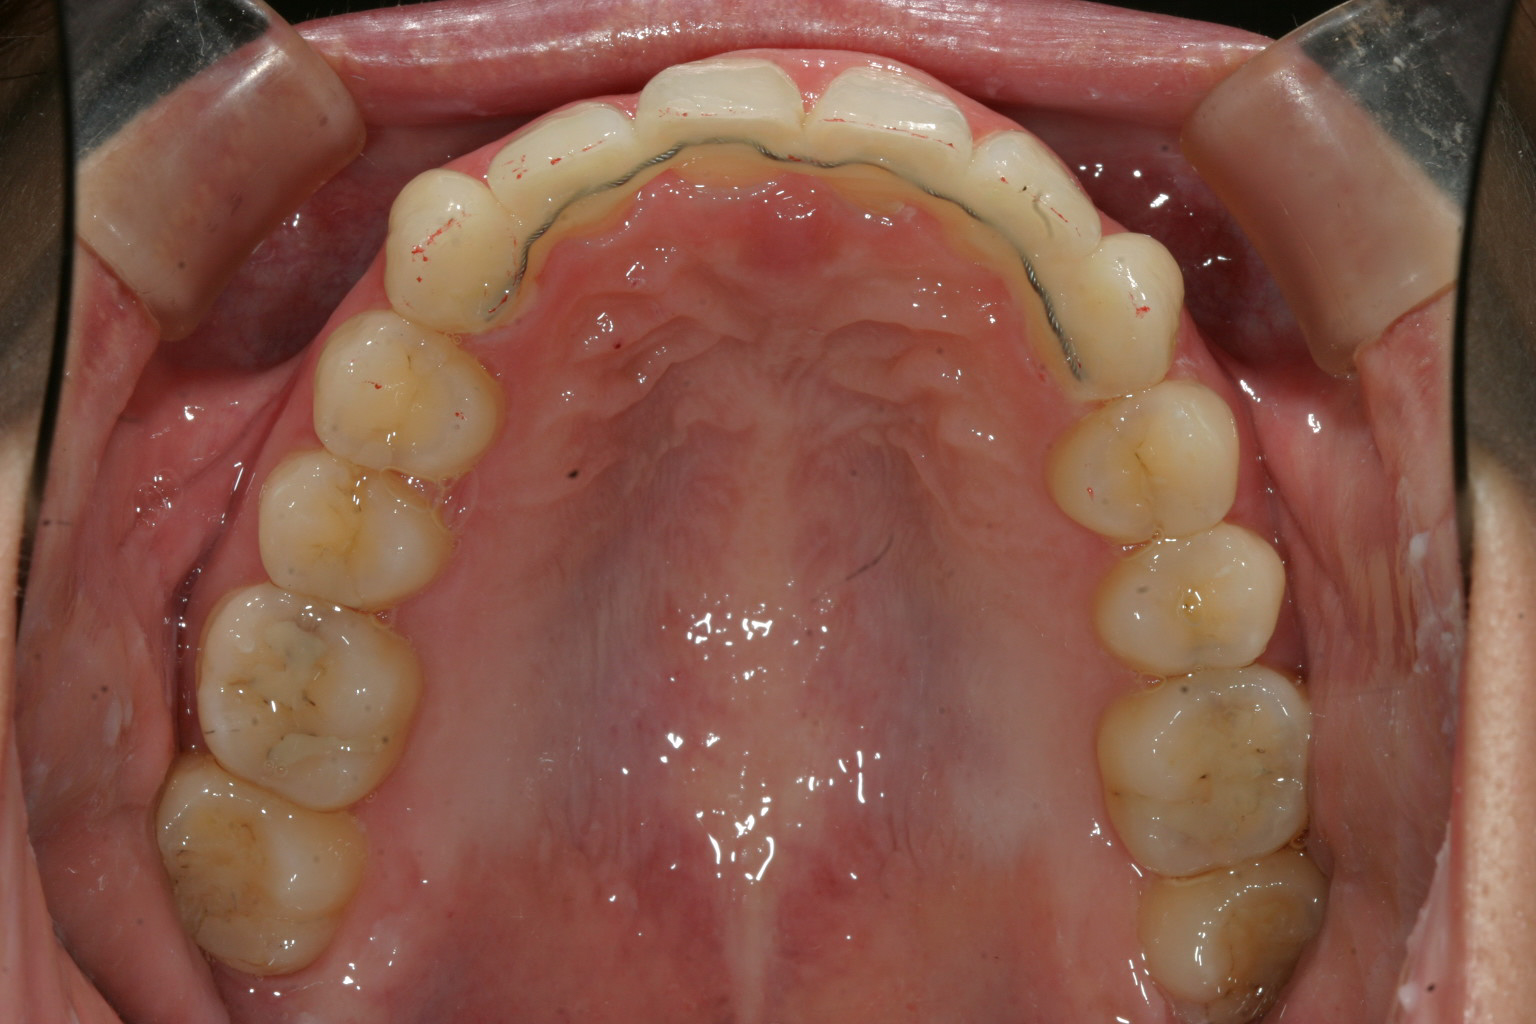

アーチを広げU字型にする事により前歯が綺麗に並びました。

こういった症例はよくあるケースでアーチの拡大する事により前歯が並び結果として出っ歯が引っ込むと言う結果に繋がりました。

もう一つ出っ歯を引き込めるためにIPR(歯と歯の間を少し削る)と言う事も行っています。これはインビザラインの特徴の一つです。

ここまで抜歯する事無く歯を引っ込めることが出来るならかなりの確率で抜歯矯正は防げる筈です。